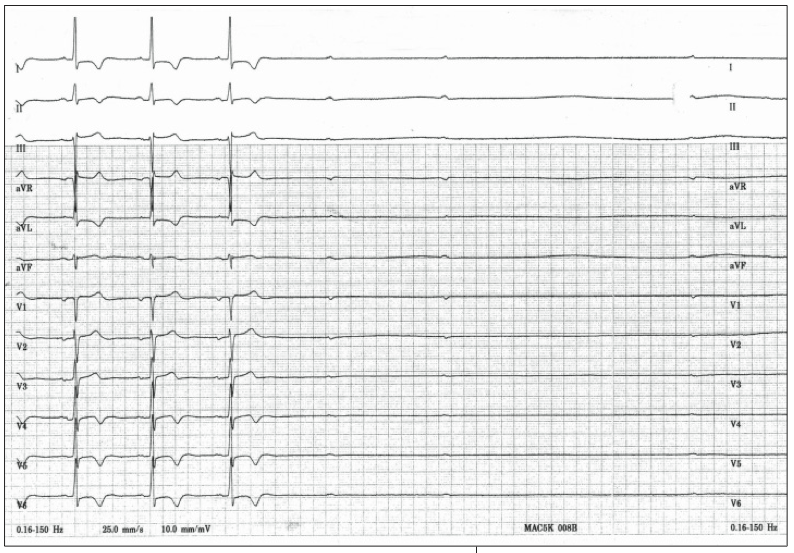

In the ED, carotid massage is performed to determine whether the patient’s symptoms can be reproduced. The 12-lead rhythm strip recorded during carotid massage is shown here.

This patient experiences high-grade atrioventricular conduction block during the carotid massage resulting in lack of conduction to the ventricle, but the sinus node eventually stops as well making complete heart block (choice A) an incomplete answer. While this patient does have slight irregularity in the beats leading up to the carotid massage, sinus arrhythmia (choice C) does not explain the long 9-second pause that is seen (Figure 1). Before the pause, the rhythm strip shows slowing and eventual cessation of sinus P wave activity, making limb lead loss unlikely (choice E). Prior to the pause, the patient has normal sinus rhythm (Figure 2) making ectopic atrial focus (choice D) an incorrect answer.